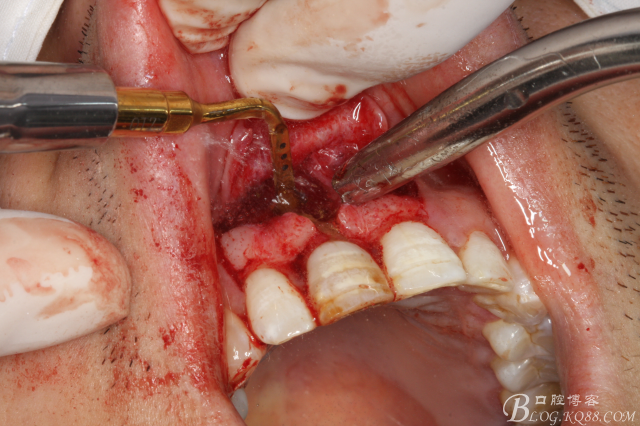

圖7.去除囊壁及肉芽組織

圖8. 觸目驚心發(fā)現(xiàn)11唇側(cè)骨壁完全缺失,根充超填。預(yù)后難以判斷。